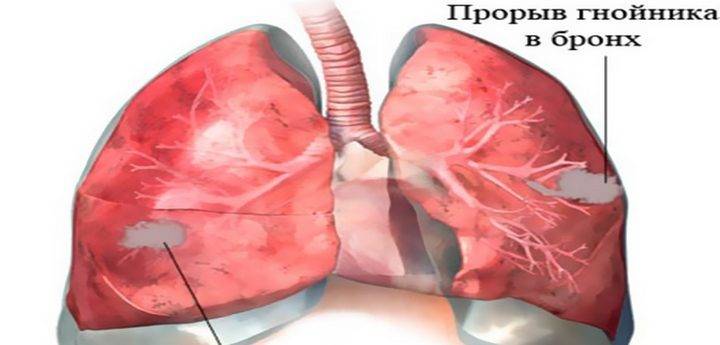

Медицинская тема: легочные осложнения при пневмонии